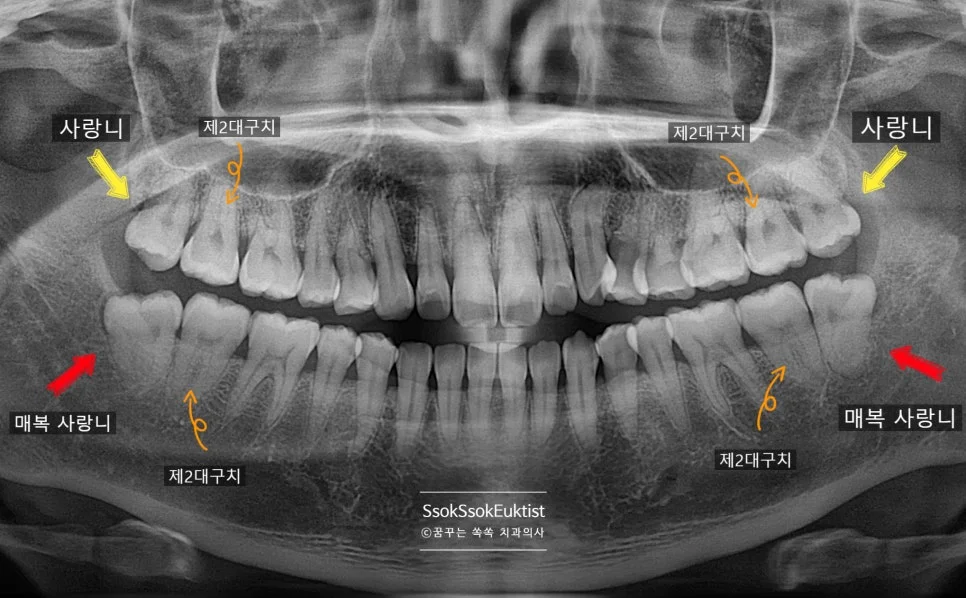

파노라마 진단

사랑니 4개 파노라마 상악 하악 매복 사랑니 제2대구치 표시

파노라마 — 상악 사랑니(노란 화살표)와 하악 매복 사랑니(빨간 화살표) 및 제2대구치 위치 확인

사랑니는 대부분 평생 사용해야 할 소중한 두 번째 큰 어금니(제2대구치) 뒤쪽 부위에 충치나 잇몸 염증을 유발합니다.

더 중요한 점은, 사랑니가 없었다면 이 두 번째 어금니의 뒷면에는 충치나 잇몸 문제가 거의 발생하지 않는다는 사실입니다.

빠르게 발치하는 게 좋은 결정이겠죠?

사랑니 4개 발치 계획 파노라마 상악 하악 화살표 표시

파노라마 — 상악(노란 화살표) + 하악(빨간 화살표) 4개 사랑니 발치 계획